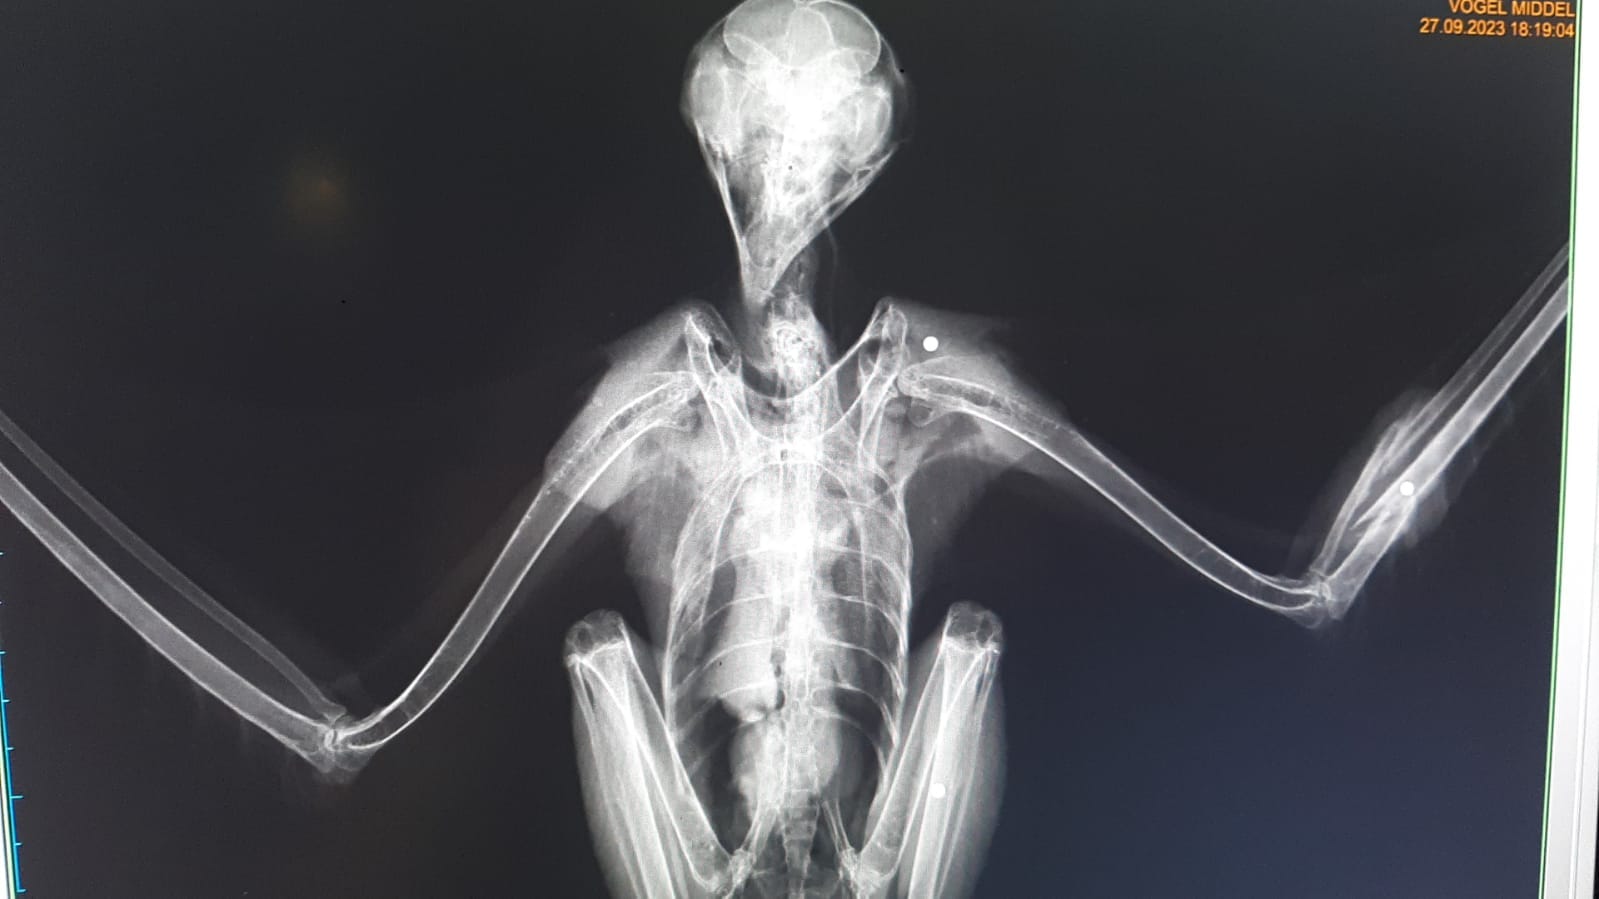

Deze ochtend kregen we telefoon vanuit Maaseik waar men langs de Maas een zeldzame velduil gevonden had die in zijn nachtelijke vlucht de prikkeldraad te laat opmerkte. Helaas zat het dier al enige tijd verstrikt en probeerde hij weg te komen. Hierdoor zijn de verwondingen zeer groot.